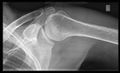

أشعة إكس

CR. shoulay film.